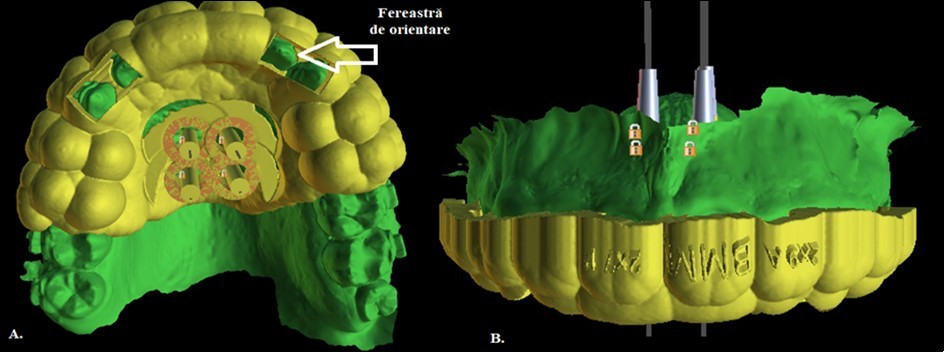

The precise position and angulation of the mini-implants is replicated by 4 cylindrical metallic guides taking into consideration the following parameters: bone thickness, soft tissue thickness and anatomical surrounding structures. The most appropriate site for the placement of mini-implants is: 3 mm lateral to the suture in the first premolar region. (Figure 3,Figure 4)

Figure 3.Positioning of the 4 mini-implants, visualized on the basis of the intraoral scan

A 3D positioning guide was designed on top of the virtual model with the final mini-implant position. (Figure 5)

Figure 5.Designing the surgical guide

The customized surgical template was 1.8 mm thick layer offset based on the teeth/mucosa/ bracket contour profiles and ranged from incisors to second premolar. The surgical template was designed to cover the entire occlusal surface. (Figure 6)

Figure 6.Custom made surgical guide with mini-implant analogs final design

Patient’s initials are engraved on the outer surface of the guide, as well as the dimensions of the mini-implants in order to provide more safety and not cause confusion during the transfer from the printing office to the dental office (Figure 6).